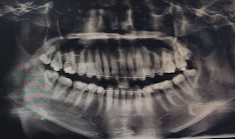

5월에 촬영하였던 파노라마 다음에는 윗니 배열시 조금 위로 당기면서 배열하기 위해

미니스크류를 식립해야 된다고 하네요!